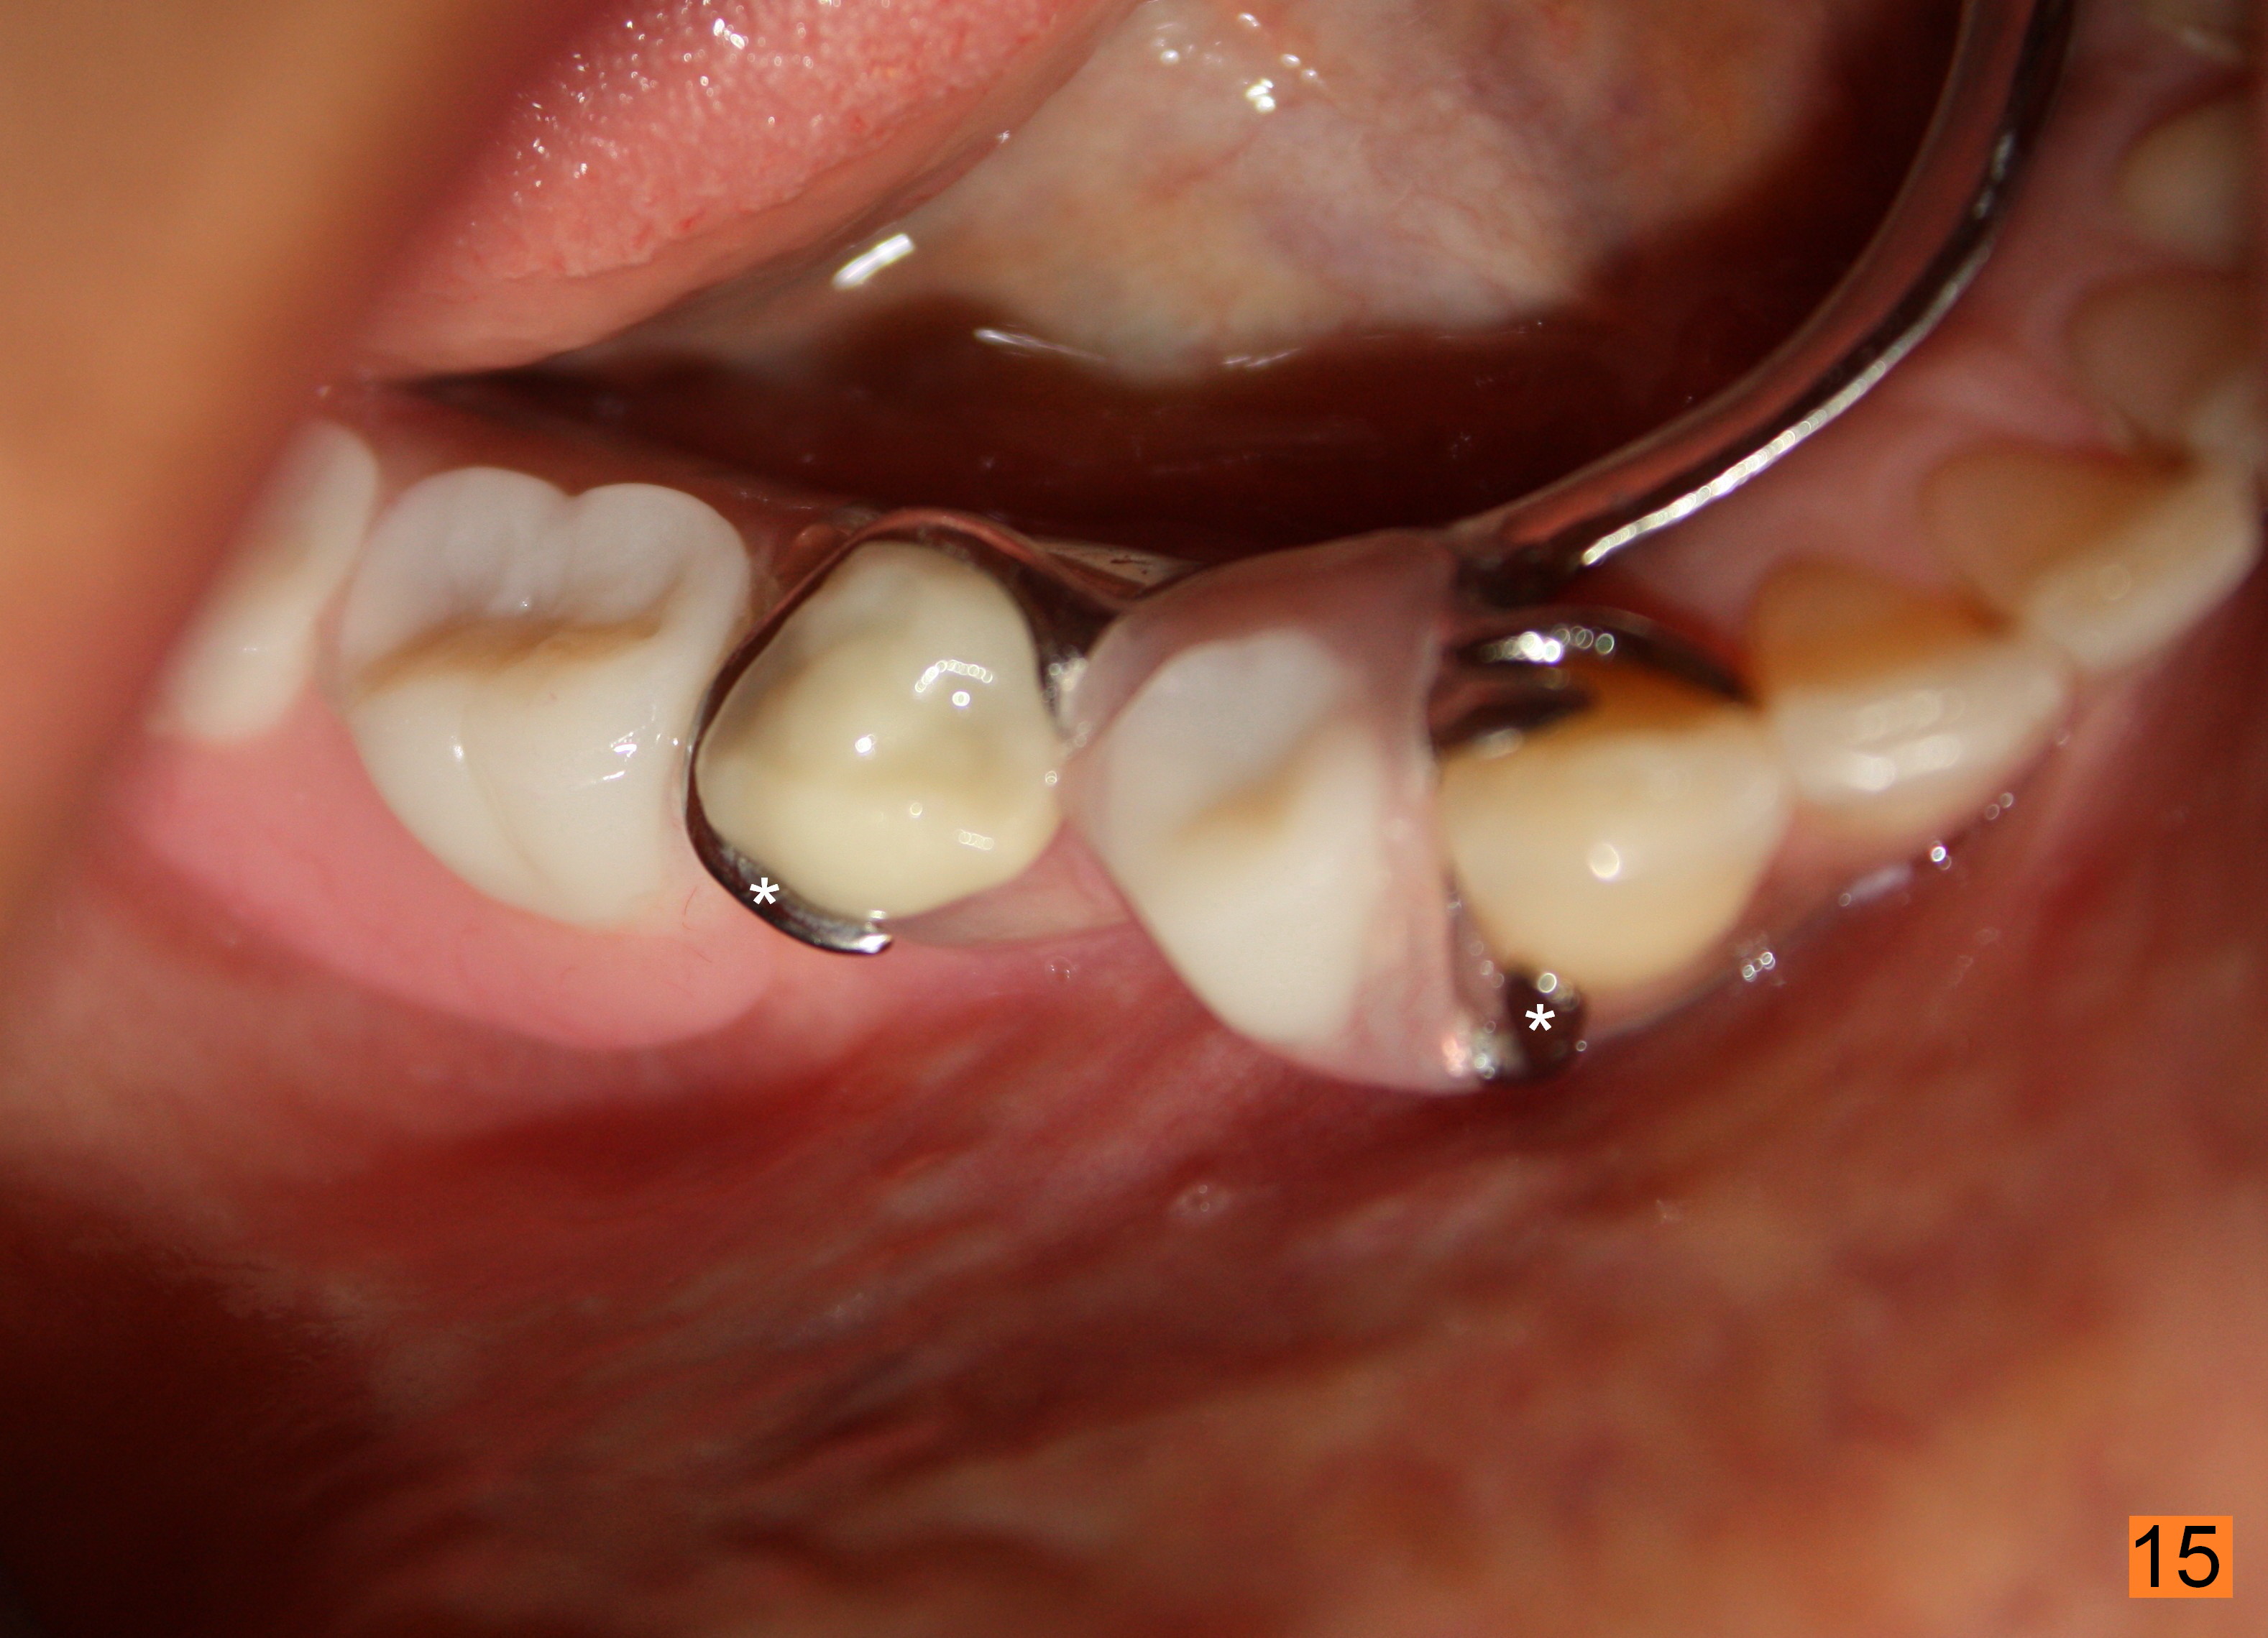

Fig.12,13 show the implant crown in function for 7 months, while Fig.14,15 for 16 months post cementation. In fact, a new RPD has been fabricated with clasp and I-bar (Fig.15 *, as compared to Fig.8,12).